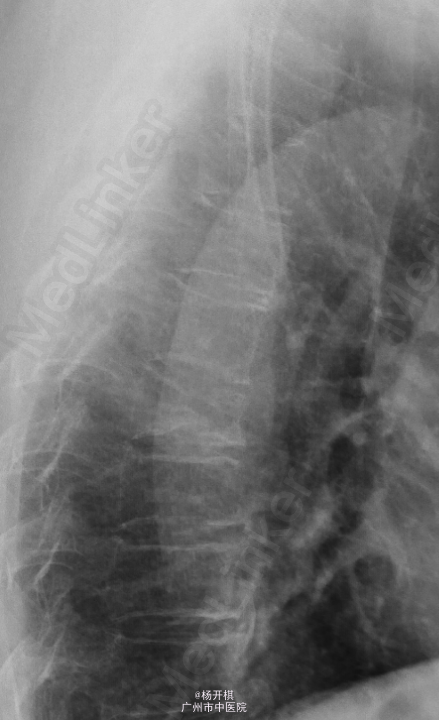

主诉:胸背部疼痛5天。 病史:老年男性,68岁。5天前在起床时突然出现胸背部剧烈疼痛,呼吸稍促,到急诊做心电图及BNP等排除心肌梗死,胸部X线示:T7压缩性骨折。建议患者入院治疗,患者拒绝,回家服药治疗。今日再次门诊就诊,疼痛严重,影响睡眠,影响活动等。患者一般情况较差。

查体:脊柱生理弯曲存在,无明显侧后凸畸形。胸12、腰1-3棘突、棘间及棘旁压痛、叩击痛,余腰、骶棘间及棘旁无明显压痛或击痛。双侧坐骨神经出口处无压痛。四肢肌张力正常,四肢感觉、肌力无明显异常。双侧膝反射及踝反射正常,双侧踝阵挛阴性。双侧Babinski 征及Oppenheim 征(-)。双侧直腿抬高试验(-),加强(-)。 辅助检查:三大常规、血生化、肝肾功能均未见明显异常。患者胸椎动力位片正常,其余重要胸椎影像学如下。

诊断:胸椎压缩性骨折(T7)。 处理:患者入院后完善相关检查,并给予对症治疗,科里术前讨论决定:拟行手术:T7经皮椎体成形术。